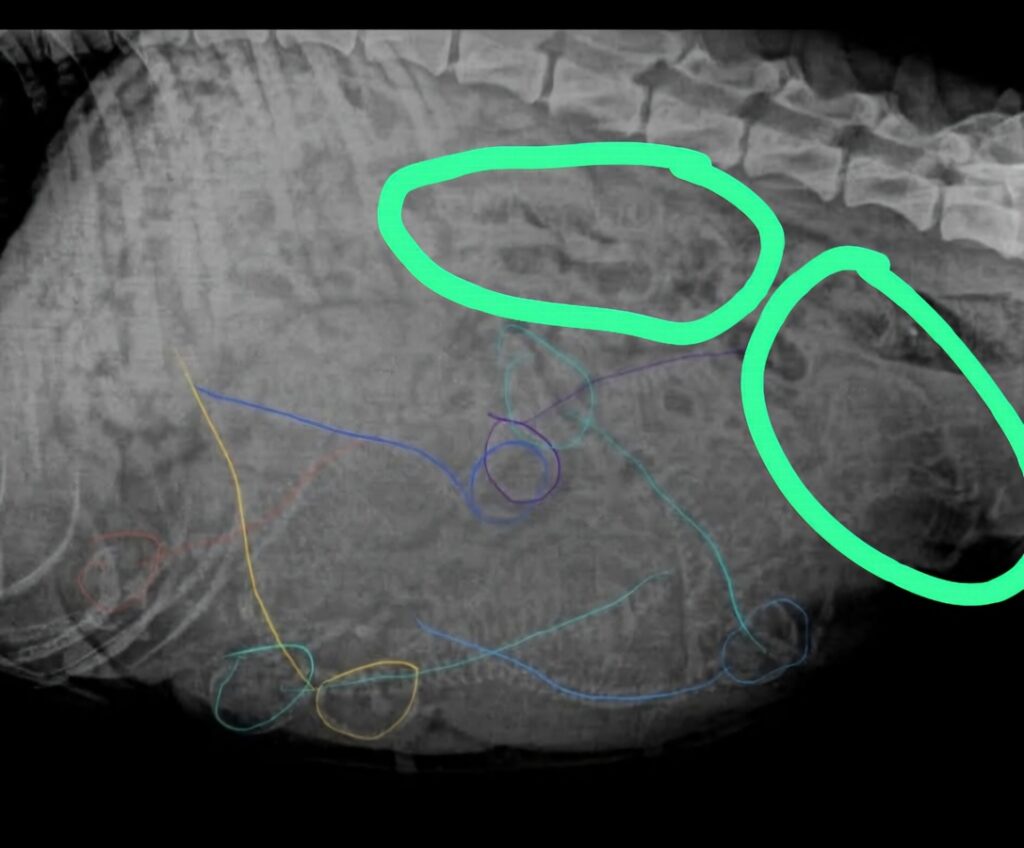

Heute war Ayoli noch mal zum Check up und Röntgen, natürlich ohne Narkose. Insgesamt hat die werdende Mama knapp 7 kg zugenommen und es geht ihr prächtig Wir erwarten 7-9 kleine Sonnenstrahlen, leider war Ayoli völlig aufgebläht, so dass man die Skelettstrukturen schlecht erkennen konnte. Die Auflösung kommt dann zum Wochenende um den 07.03. rum.